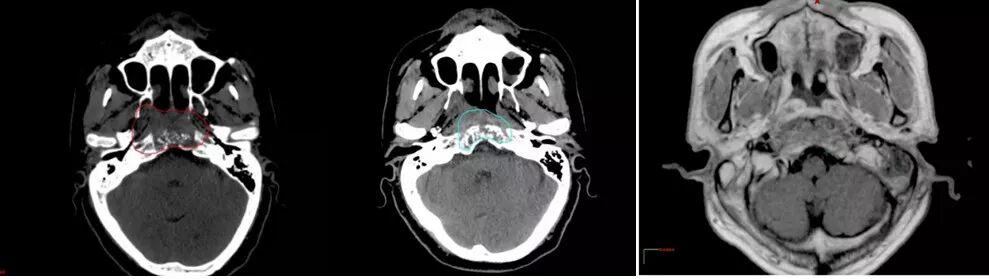

质子治疗鼻咽癌肿瘤缩小70%

患者:男,55岁

因鼻塞2年余,涕中带血半年,头痛20余天,入院诊断为鼻咽癌(低分化鳞癌)复发,给予质子治疗。治疗1个月后复查(中),肿瘤明显缩小,无不良反应;治疗7个月后MR图像(右),肿瘤缩小70%。

治疗前CT图像(左)

治疗1个月后复查(中),肿瘤明显缩小,无不良反应

治疗7个月后MR图像(右),肿瘤缩小70%